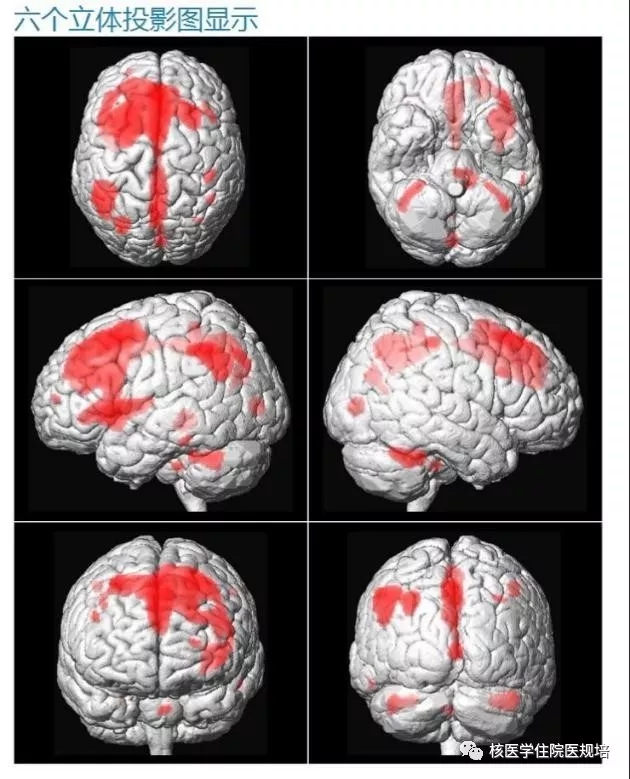

患者封闭视听15分钟后注射18F-FDG,随后在视听封闭状态下静卧休息;注射后1小时使用脑部专用检查程序行脑图像采集。经计算机重建处理后,获得三方位断层图像及SPM软件分析3D图,结果显示:大脑皮质形态正常,中线结构居中;双侧大脑半球皮质及神经核团FDG摄取不均匀性减低,以左侧额叶、顶叶及丘脑为著(图2-3);另可见全脑脑室、脑沟、脑池普遍增宽(图4)。

2

3

1.脑灰质及神经核团FDG代谢不均匀减低,以左侧额叶、顶叶及丘脑代谢减低为著,可符合皮质基底节变性表现

18F-FDG PET/CT显像反映的是脑组织葡萄糖代谢水平,不同疾病累及脑组织的部位不同,PET/CT显像会有其特征性的表现。脑部不对称性葡萄糖代谢改变对于CBD 的诊断和鉴别诊断具有重要临床意义,即严重受累肢体对侧的脑区存在明显葡萄糖代谢减低。虽然以往研究所报道的脑异常代谢区分布有所差异,但CBD患者总会出现皮质代谢减低,多见于严重受累肢体对侧的额叶、顶叶和丘脑,而约一半患者并不存在基底节代谢减低。本病例中的患者右侧肢体肌张力增高明显,FDG PET/CT显像显示左侧额叶、顶叶及丘脑代谢减低,与既往报道结果也一致[1],故可符合CBD表现,且提示该病变仅位于皮质,基底节并未受累。